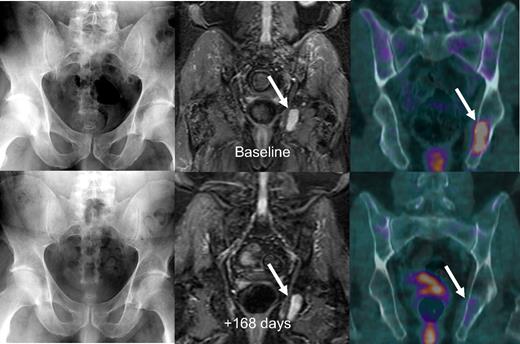

Figure 3 shows imaging sequences of a patient with stage IIIA IgA κ myeloma who in May 2005 was untreated when referred to our institution and enrolled in Total Therapy 3. Baseline MRI and FDG-PET/CT imaging studies showed active focal intramedullary disease. Approximately 6 months later, in October 2005, the patient had achieved n-CR status by laboratory criteria with near-complete resolution of abnormal FDG uptake on PET. The representative left ischial lesion's maximum SUV decreased from a baseline value of 4.1 to 1.2 and was considered resolved as the uptake was similar to background marrow activity, with resolution of PET-FL and suppression of FDG uptake (SUV-FL). Nearly 3 years later, the patient has retained n-CR status.

Untreated myeloma patient with time-concordant MBS, MRI, and FDG-PET/CT studies. Baseline imaging studies (top row) showed no osteolysis on MBS (top left), several foci on STIR-weighted MRI images with the largest in the left ischium (top middle), and 2 foci on FDG-PET/CT imaging (top right) with the largest again in the left ischium with a maximum SUV of 4.1. The patient was in near-complete remission 168 days later, with a significant decrease in focal activity in the left ischial lesion on PET (bottom right).